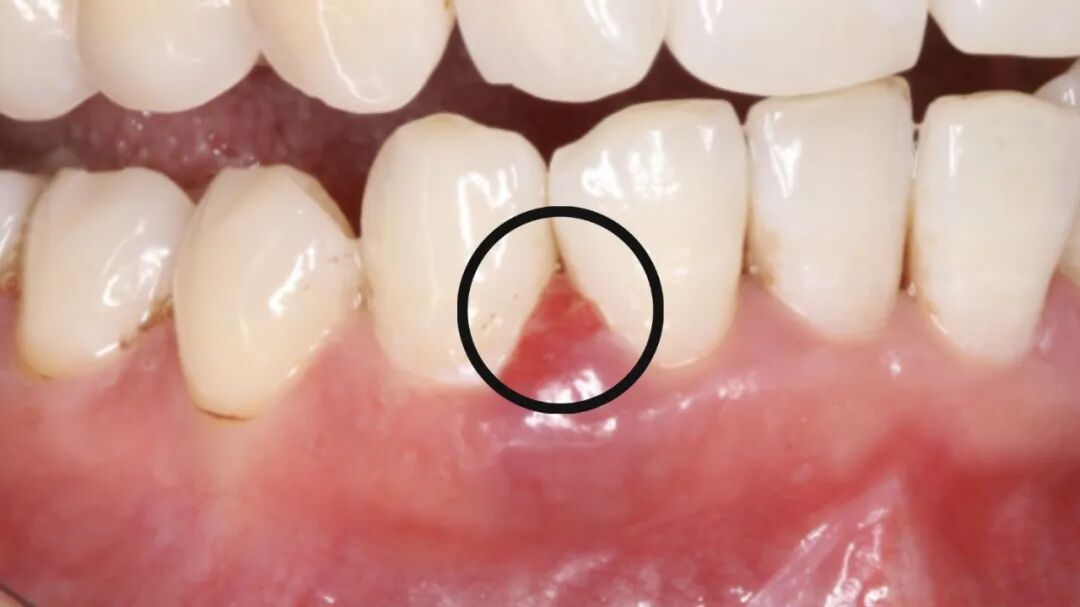

牙龈健康的恢复:炎症消退

如果在治疗前,你的牙龈因为炎症而肿胀,这种肿胀会暂时“遮住”一部分牙缝。在治疗后,随着炎症消退,牙龈会恢复到健康状态并贴合在牙齿表面,这时牙缝也会显得更加明显。

治疗前

治疗后